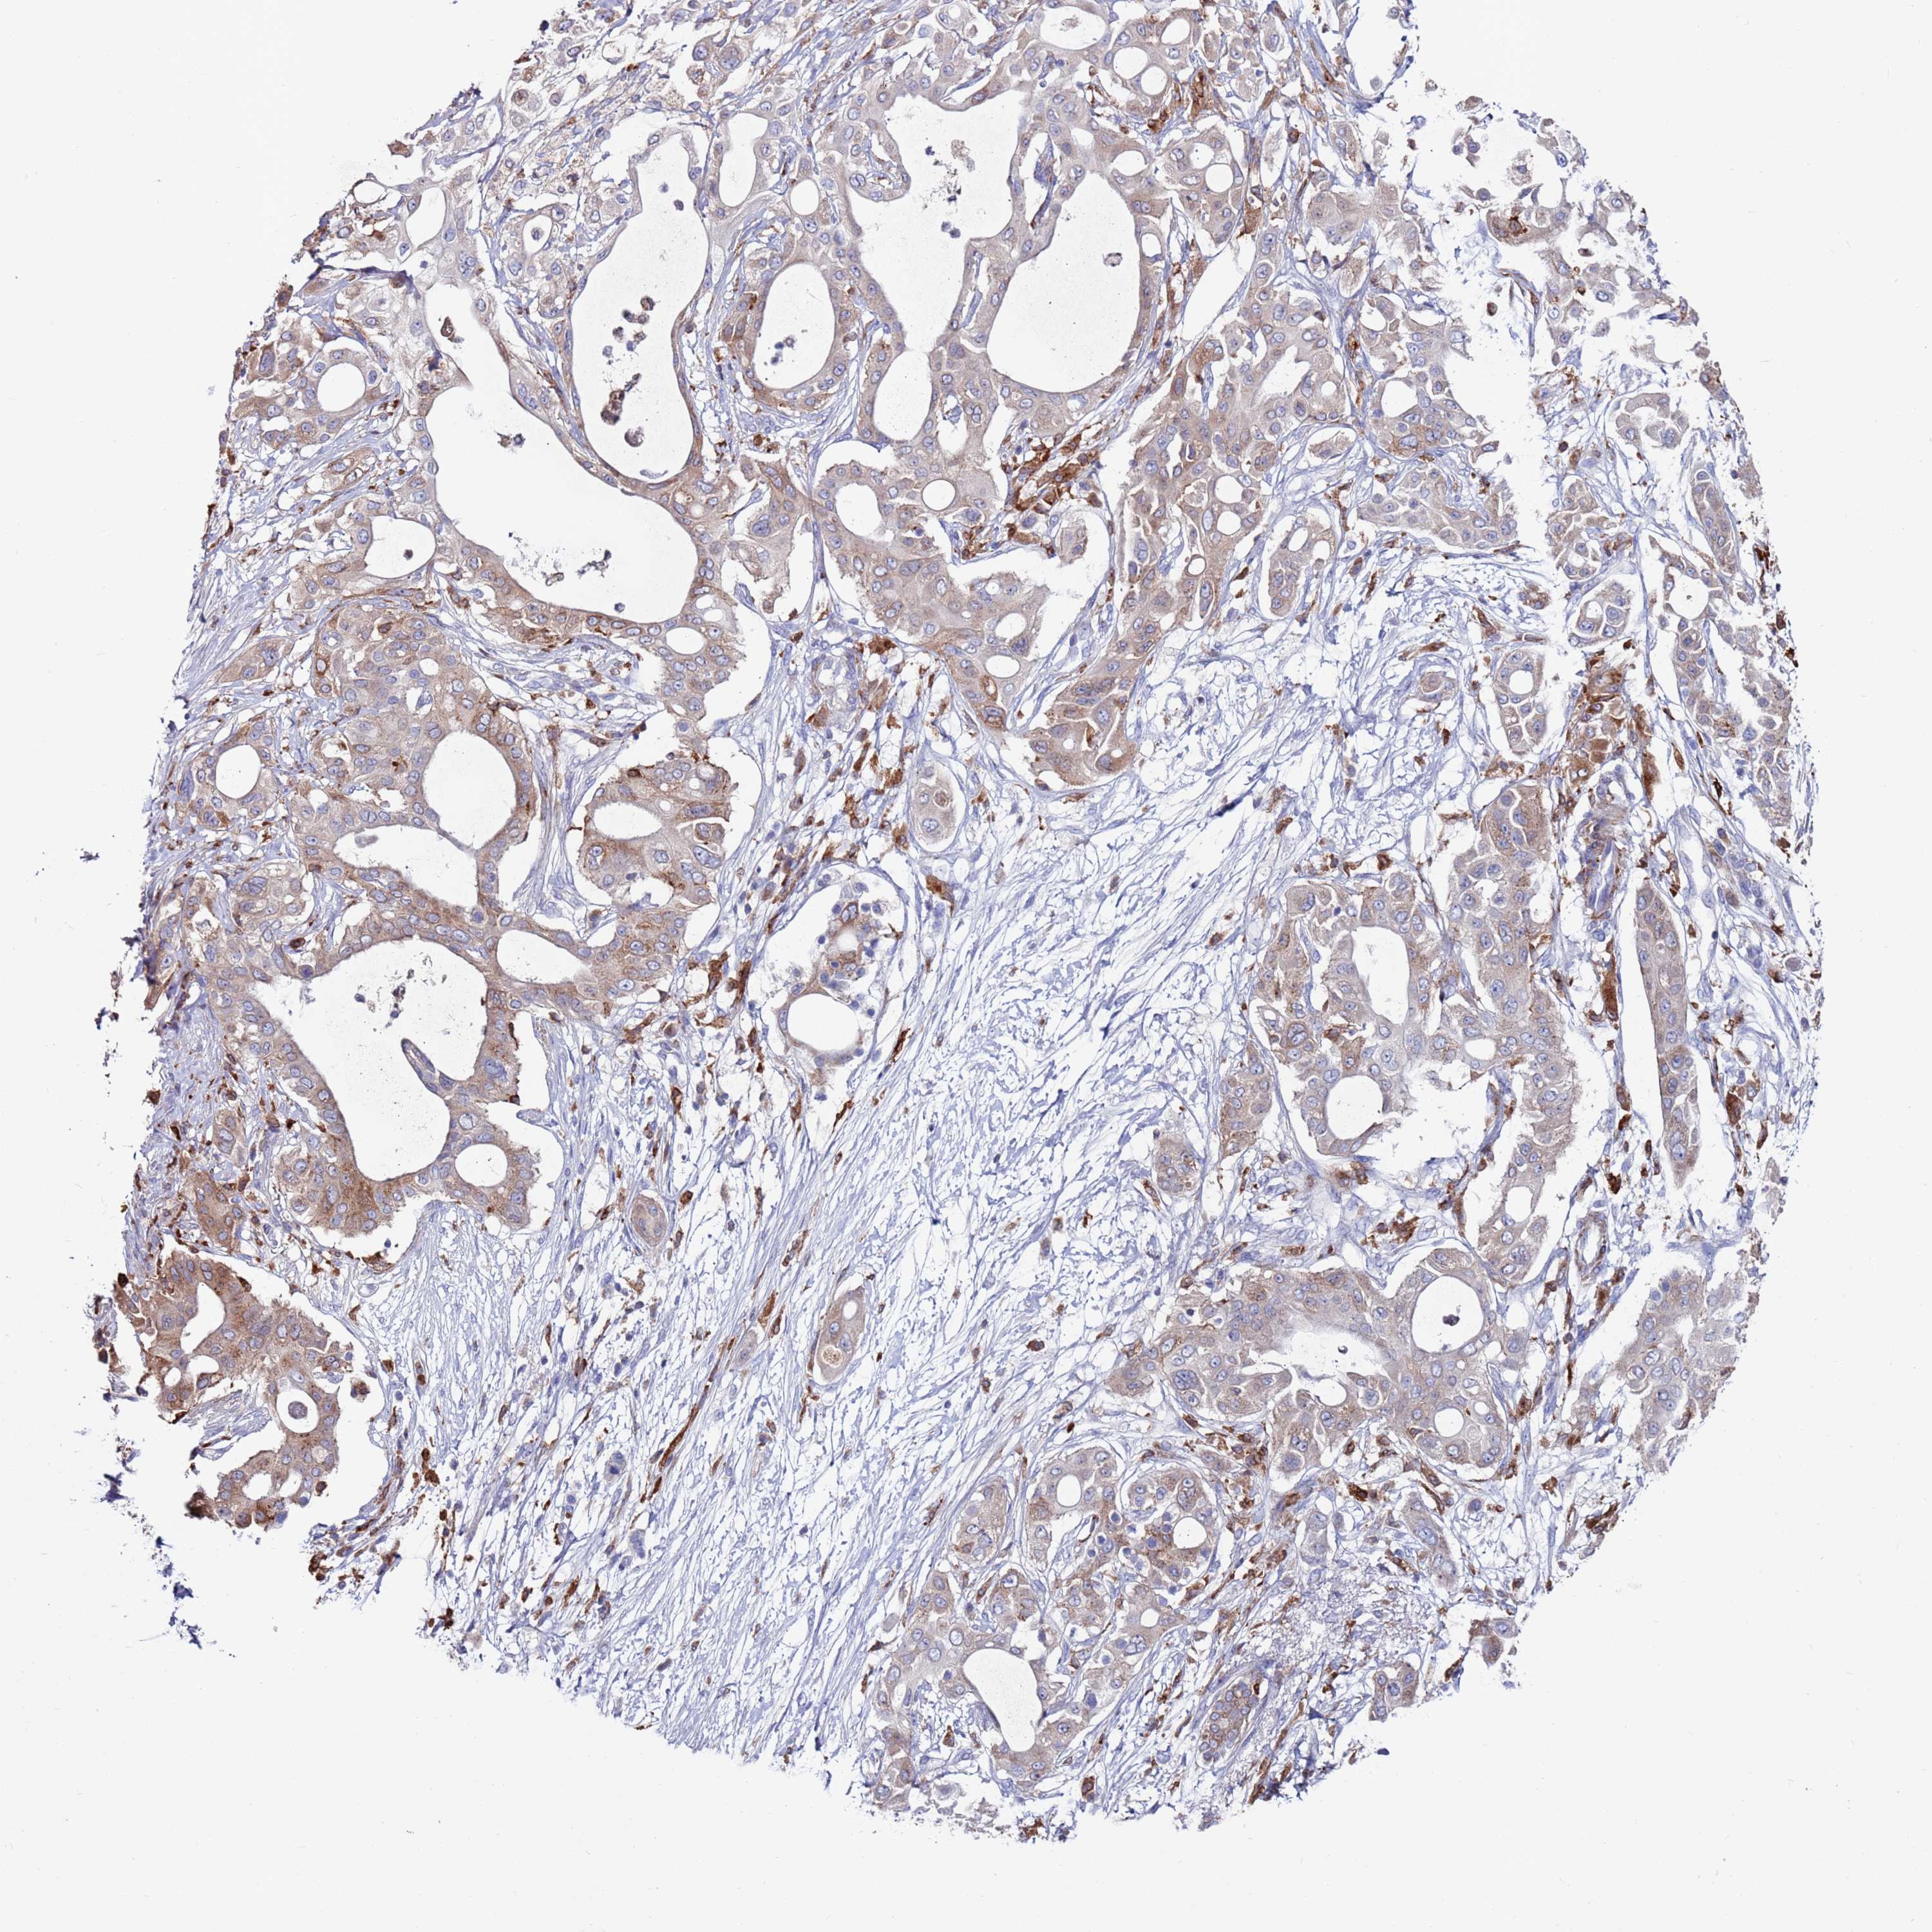

PANCREATIC CANCER - Protein expressioni

A mouse-over function shows sample information and annotation data. Click on an image to view it in a full screen mode. Samples can be filtered based on level of antibody staining by selecting one or several of the following categories: high, medium, low and not detected. The assay and annotation is described here.

Note that samples used for immunohistochemistry by the Human Protein Atlas do not correspond to samples in the TCGA dataset.

Antibody stainingi

Antibody staining in the annotated cell types in the current human tissue is reported as not detected, low, medium, or high, based on conventional immunohistochemistry profiling in selected tissues. This score is based on the combination of the staining intensity and fraction of stained cells.

Each image is clickable and will lead to virtual microscopy that enables deeper exploration of all samples and also displays staining intensity scores, fraction scores and subcellular localization as well as patient and tissue information for each sample.

Antibody HPA041647

Antibody HPA044218

Staining

High

Medium

Low

Not detected

Intensity

Strong

Moderate

Weak

Negative

Quantity

>75%

75%-25%

<25%

None

Location

Nuclear

Cytoplasmic/membranous

Cytoplasmic/membranous,nuclear

Adenocarcinoma, NOS